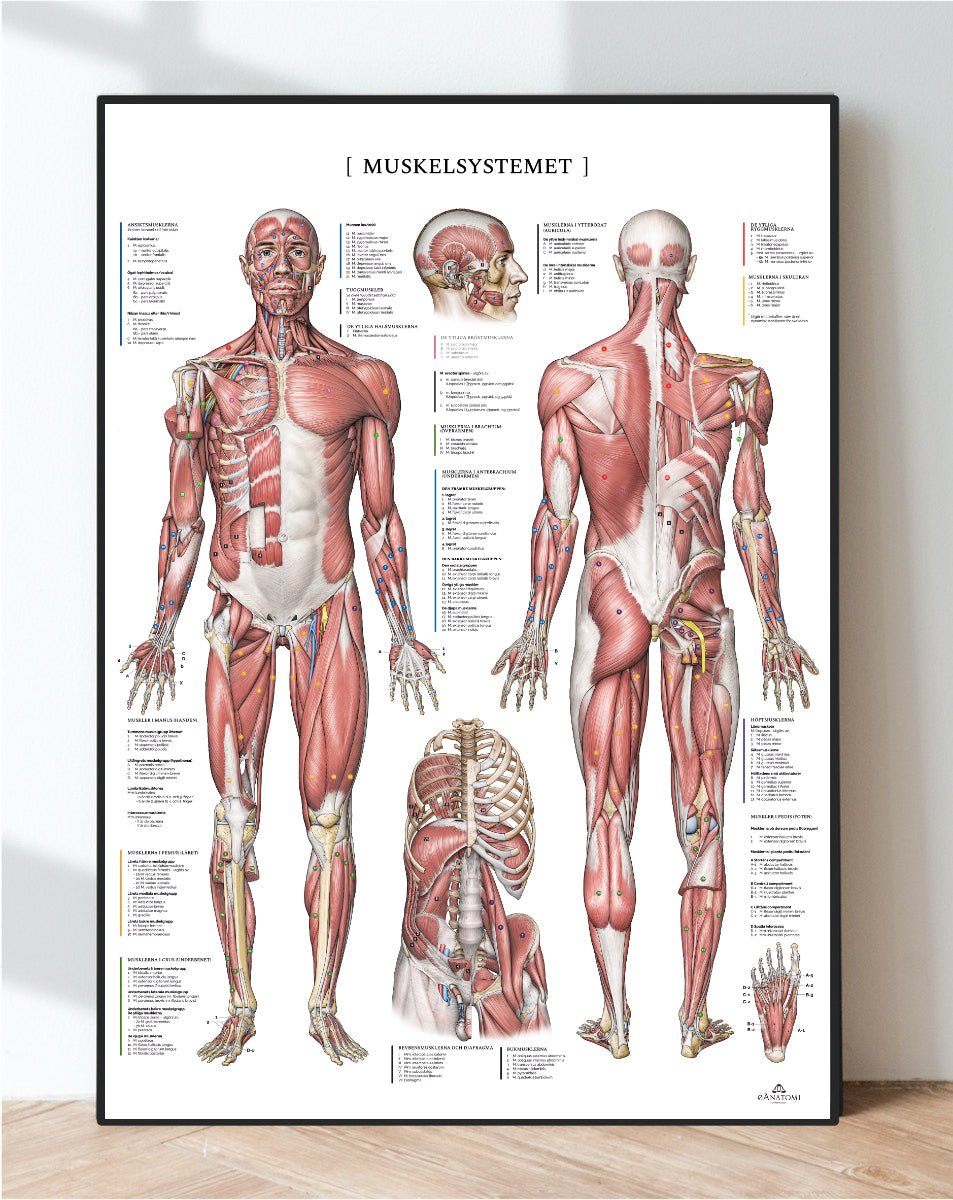

Andra produkter utvalda speciellt för dig

Vårt anatomiska produktsortiment